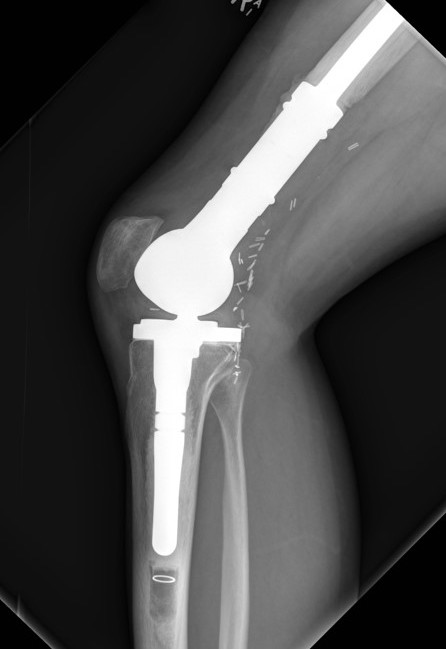

Management

Algorithm

1. Neoadjuvent chemotherapy

2. Restage

3. Surgical resection

4. Chemotherapy

5. Radiotherapy - if margins inadequate

Wide Resection - limb salvage / amputation

2 cm margin of normal tissue if able